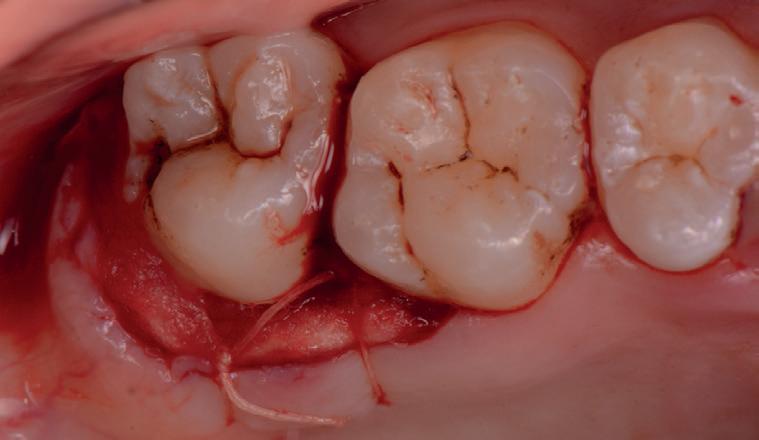

RECONSTITUIREA țesuturilor moi periimplantare. Scopul acestui raport de caz este de a demonstra procedurile chirurgicale utilizate pentru corectarea unui defect al țesuturilor moi periimplantare folosind țesutul moale interdentar în combinație cu tuberozitatea ca locație donatoare de țesut conjunctiv, utilizând o abordare prin tunelizare într-o zonă estetică.